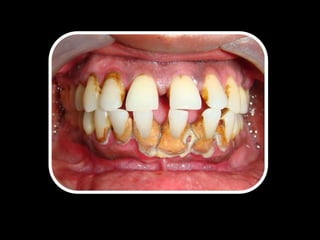

Necrosis Pulpar / Periodontitis A. Crónica Supurativa 11

CLÍNICAMENTE RADIOGRÁFICAMENTE

• Caries grado 3

• Pigmentación coronal

(Gris-Café)

• Fistula dental

• Exudado a través de la

fistula o el conducto

radicular

• Inflamación gingival

• Movilidad grado 1-2

• Zona radiolucida (Apical)

• Ensanchamiento del ELP

• Es posible realizar

fistulografía

PRUEBAS DE SENSIBILIDAD ANAMNESIS

• (-) Pruebas térmicas

• (+) Percusión Vertical

• (+) Percusión H.

• (+) Palpación

• Dolor a la masticación

• Sintomático o

asintomático

• Refiere sintomatología,

que no sede

completamente con

analgésicos comunes

(No pudo dormir)

TRATAMIENTOS

• Tratamiento endodóntico

• Extracción dental